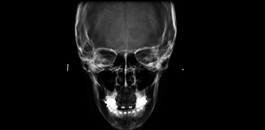

Avaliação das vias aéreas.

Avaliação das estruturas da face.